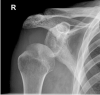

Isolated deltoid paralysis is a rare pathology that can occur after axillary nerve injury due to shoulder trauma or infection. This condition leads to loss of deltoid function that can cause glenohumeral instability and inferior subluxation, resulting in rotator cuff muscle fatigue and pain. To establish dynamic glenohumeral stability, a novel technique was invented. Humeral suspension is achieved using a double button implant with non-resorbable high strength cords between the acromion and humeral head. This novel technique was used in two patients with isolated deltoid paralysis due to axillary nerve injury. The results indicate that the humeral suspension technique is a method that supports centralizing the humeral head and simultaneously dynamically stabilizes the glenohumeral joint. This approach yielded high patient satisfaction and reduced pain. Glenohumeral alignment was improved and remained intact 5 years postoperative. The humeral suspension technique is a promising surgical method for subluxated glenohumeral joint instability due to isolated deltoid paralysis.